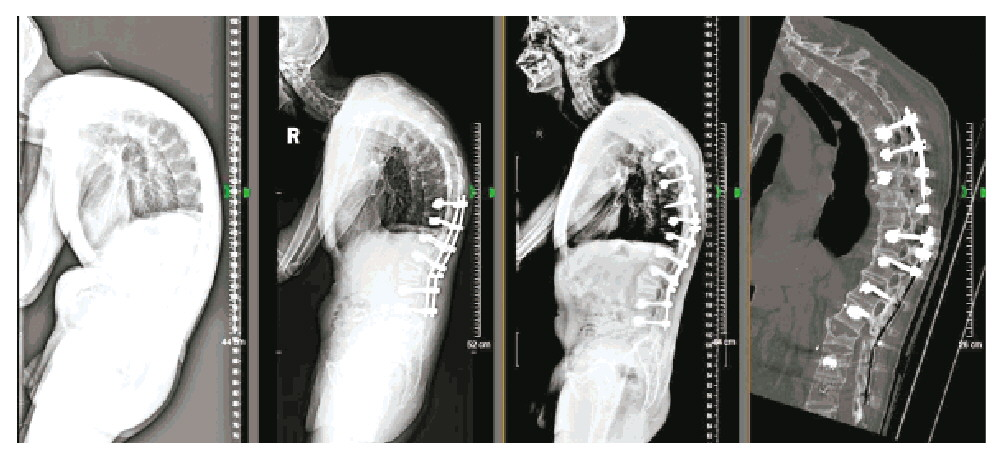

与小明父母沟通并取得手术同意后,张辉主任和张力副主任仔细评估手术风险,详细规划手术方案,进行了充分的术前准备,还借助3D打印技术,为小明制定了精密的脊柱畸形矫形手术计划。

手术历时6小时顺利完成,畸形的脊柱被拉直,心肺功能也不会受骨骼畸形限制了。术后第5天,佩戴夹克式背架后,小明终于可以“抬头挺胸”下地行走了,并且身高还长了4cm。